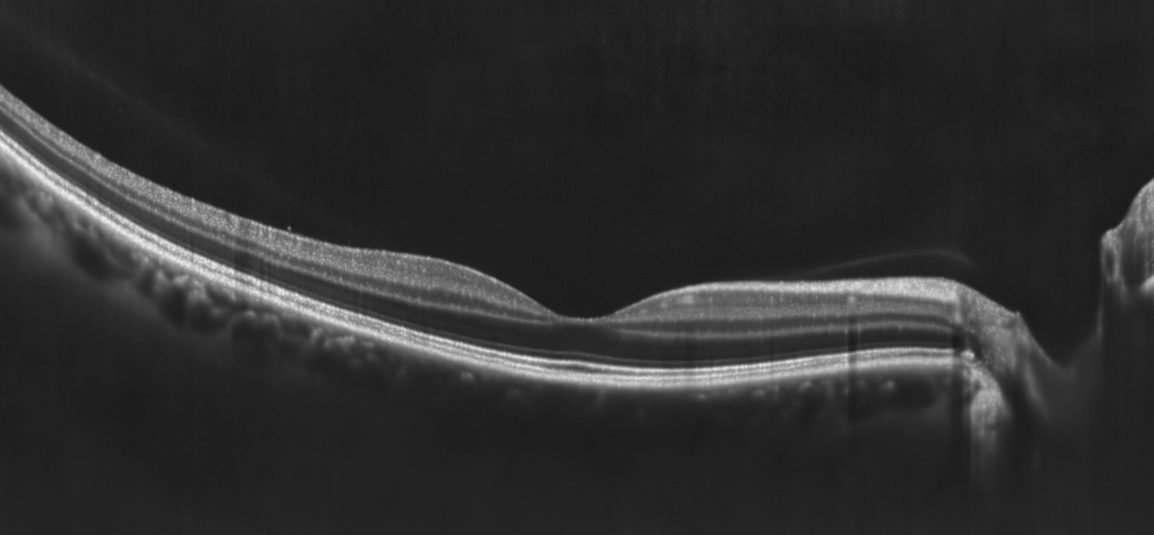

Netthinne uten druser til venstre (gjengitt med tillatelse)

Netthinne med druser til høyre (gjengitt med tillatelse)